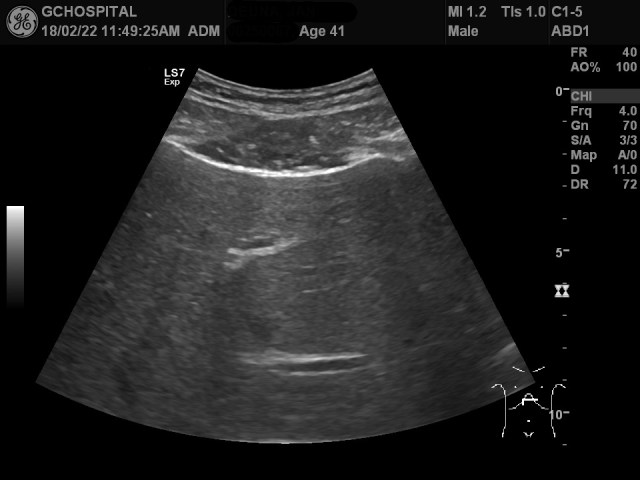

반면, 위 영상은 간에 별다른 이상이 없이 건강검진을 위해 내원한 환자의 간초음파영상입니다.

9MHz frequency의 선형탐촉자로 본 liver surface영상인데, 앞서와는 달리 매끈한 간 피막을 확인할 수 있습니다.